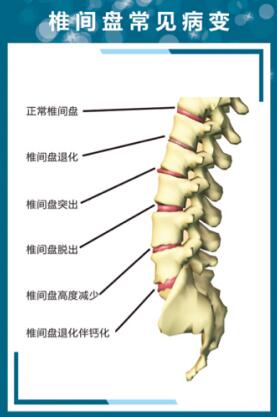

我们通过现代医学X光片、Ct、磁共振影像显示,病位诊断看到的只是椎骨、生理曲度、椎骨间盘结构问题。

颈椎、腰椎间盘突出症是人们在长期的工作、生活中久坐不愿活动及对筋肉劳损、挫伤的举止、习性产生的伤痛感觉无所谓,没有放在心上,殊不知,受损筋肉会能用极强的记忆力,把所受伤害储存积累下来,把其不堪重辱变成强烈的秋后算帐来报复伤其者。筋肉在长年累月的受伤害、性能退行下,影响气血运行,失却气血、津液的荣润,变得硬化、粘连、挛缩、钙化、失去韧性,失却平衡,不能够很好地保护骨柱,关节,再加上不正确的姿势或在外力作用下,出现筋挛缩、筋强、筋急、筋出槽、骨错缝、椎间盘突出、骨小关节紊乱、椎体侧弯或变直,生理结构、力线功能变异现象。筋肉、经络、血管、津液通道、骨柱、关节,扭曲、变形、相互挤压、相互绞缠、相互影响⋯⋯恶性循环状况,造成的西医医学名一一椎间盘突出临床诸痛。

我在上面讲过了,椎间盘突出症是"筋出槽、不能固骨、骨错缝、形态失衡"造成的症疾,不是大家的骨头突出,是支撑我们上肢"脊梁骨"两节椎骨之间形同圆盘状的夹层组织,西医医学名一一椎间盘突出了,椎间盘如同承重墙两块砖间的水泥沙灰夹层,其外围是坚硬性的纤维环,包裹着含水量极高、富有弹性的"果冻”状组织,西医医学名一一䯝核而组成。椎间盘环裹的纤维环在受退行、外力等因素的影响作用下出现凸隆、破裂,髓核顺势从损伤处凸隆、结构呈膨出状态;从破裂处挤溢出来,生理结构呈出壳突出状态。就如同自行车外胎出现破损、内胎露出来样的形态。